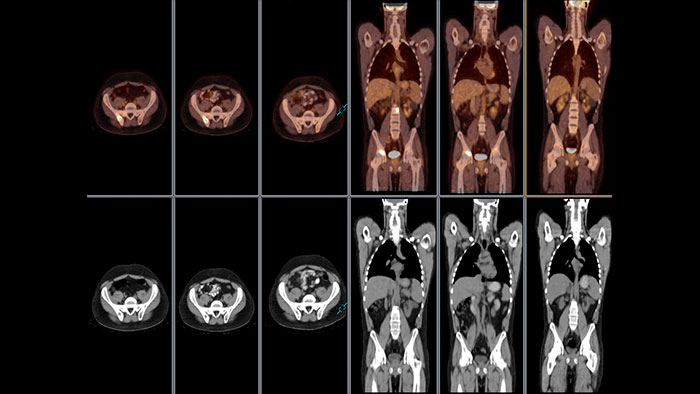

Enhanced user experience for NM reading

Designed to solve your clinical challenges and improve productivity when viewing PET\CT, SPECT, SPECT\CT and planar images. Optimized workflow for handling multiple studies and quantifying findings.

Benefits

NM Review provides a powerful MI and multi-modality image review and analysis environment for clinical evaluation of MI planar, SPECT, SPECT/CT, PET/CT, and PET/MR examinations.